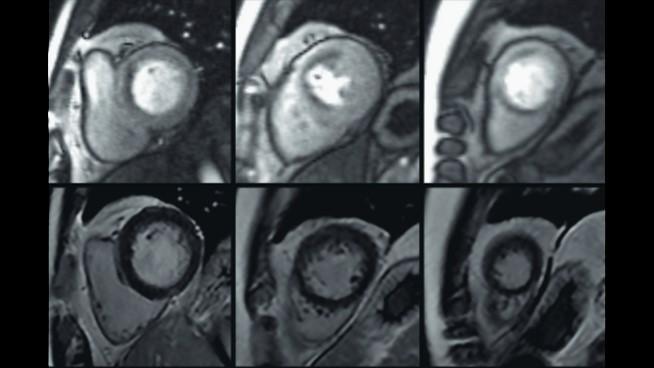

A magnetic resonance imaging (MRI) scan is an imaging test that uses powerful magnets and radio waves to provide detailed pictures of the inside of your body. MRI differs from other imaging modalities such as CT and X-ray, because it does not use radiation. MRI scans use advanced technology to create cross-sectional images of bones, organs, and tissues. These images help doctors diagnose and monitor a wide range of conditions—from injuries and infections to cancer and heart disease.